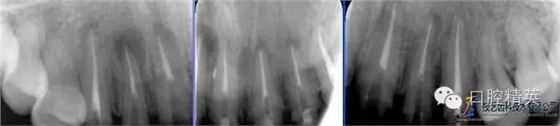

術(shù)前全景片

640.webp (4).jpg

術(shù)前根尖片

640.webp (5).jpg

術(shù)后根尖片

640.webp (6).jpg